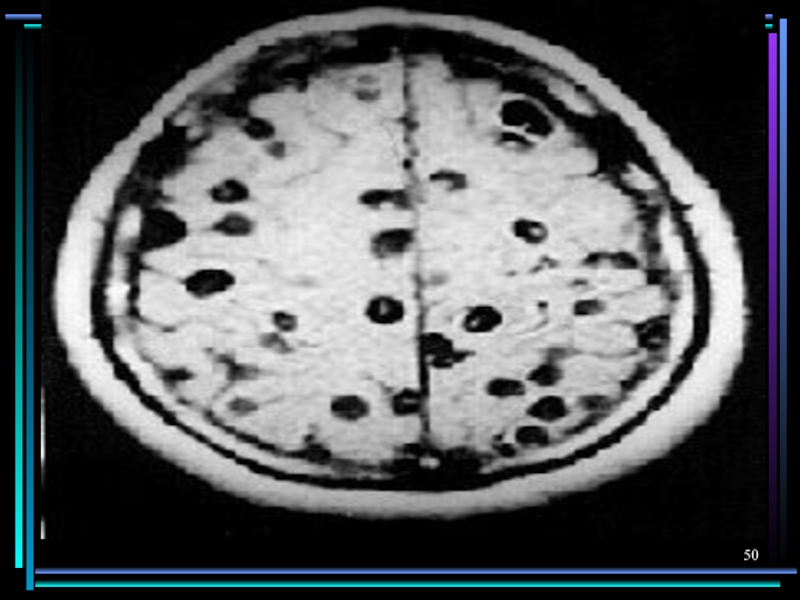

Слайд 47Поражение нервной системы

Трихинеллез

Эхинококкоз

Цистицеркоз

Токсокароз

Стронгило-идоз

Очаговые васкулиты, менингит, под-корковый энцефалит, полинейропатия

Астено-депрессивный синдром, психоз

Симптомы сдавления

вещества голов-ного и спинного мозга, симптомы повышения внутричерепного давления, эпилепсия, энцефалопатия

Гранулемы в головном мозге у детей могут проявляться эпиприступами.

Менингоэнцефалит при выраженном иммунодефиците

Поражение нервной системыТрихинеллезЭхинококкозЦистицеркозТоксокарозСтронгило-идозОчаговые васкулиты, менингит, под-корковый энцефалит, полинейропатияАстено-депрессивный синдром, психозСимптомы сдавления вещества голов-ного и спинного мозга, симптомы